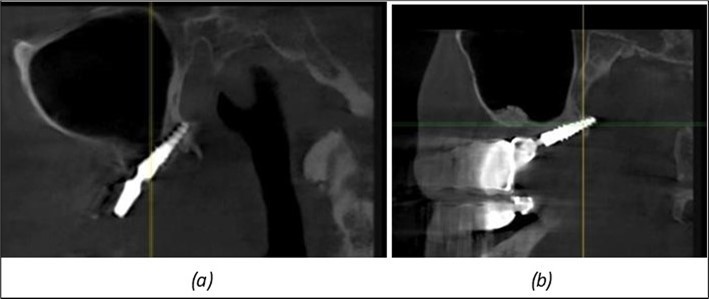

June 2022: Patient presented to our clinic for immediate-loading implant treatment At the time of presentation in 06. 2022, radiologically, advanced peri- implantitis is observed around the implants, with loss of native bone in the affected distal areas (Figure 1)

Figure 1.Panoramic overview picture before rehabilitation 06.2022

Figure 8.(a), (b) Sinus lift and grafting area with two stage implants before their removal. (c) area of fixation of BCS and TPG implants, avoiding the sinus lift and grafting area

Figure 9.Implants in the pterygoid plateau area: (a) TPG implant fixed in the maxillary-sphenoid junction area, quadrant 1; (b) TPG implant fixed in the maxillary-sphenoid junction area, quadrant 2.